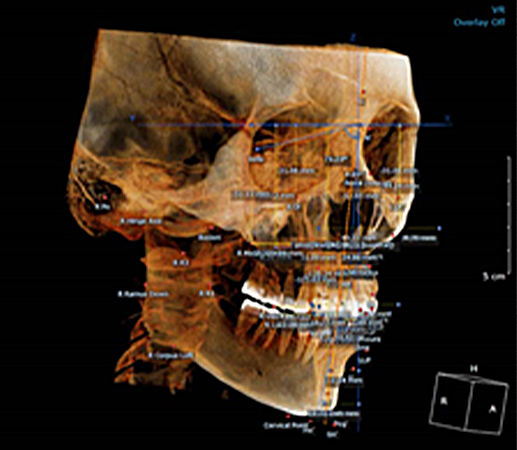

걸포탑치과는 디지털 장비를 활용하여 치아뿌리 길이, 모양, 잇몸뼈의 두께와 밀도 등 환자의 구강 상태를 파악합니다. 환자에 맞는 맞춤 임플란트 식립을 계획해드립니다.

계획된 대로 심는 네비게이션 임플란트

우리에게 올바른 길을 알려주는 네비게이션처럼 디지털 기술을 통해 최적의 수술 경로를 알려주는 네비게이션 임플란트. 3D 모의 수술을 통해 식립 위치를 정확하게 파악하고 오차 없이 식립 가능한 체계적인 디지털 임플란트 입니다.